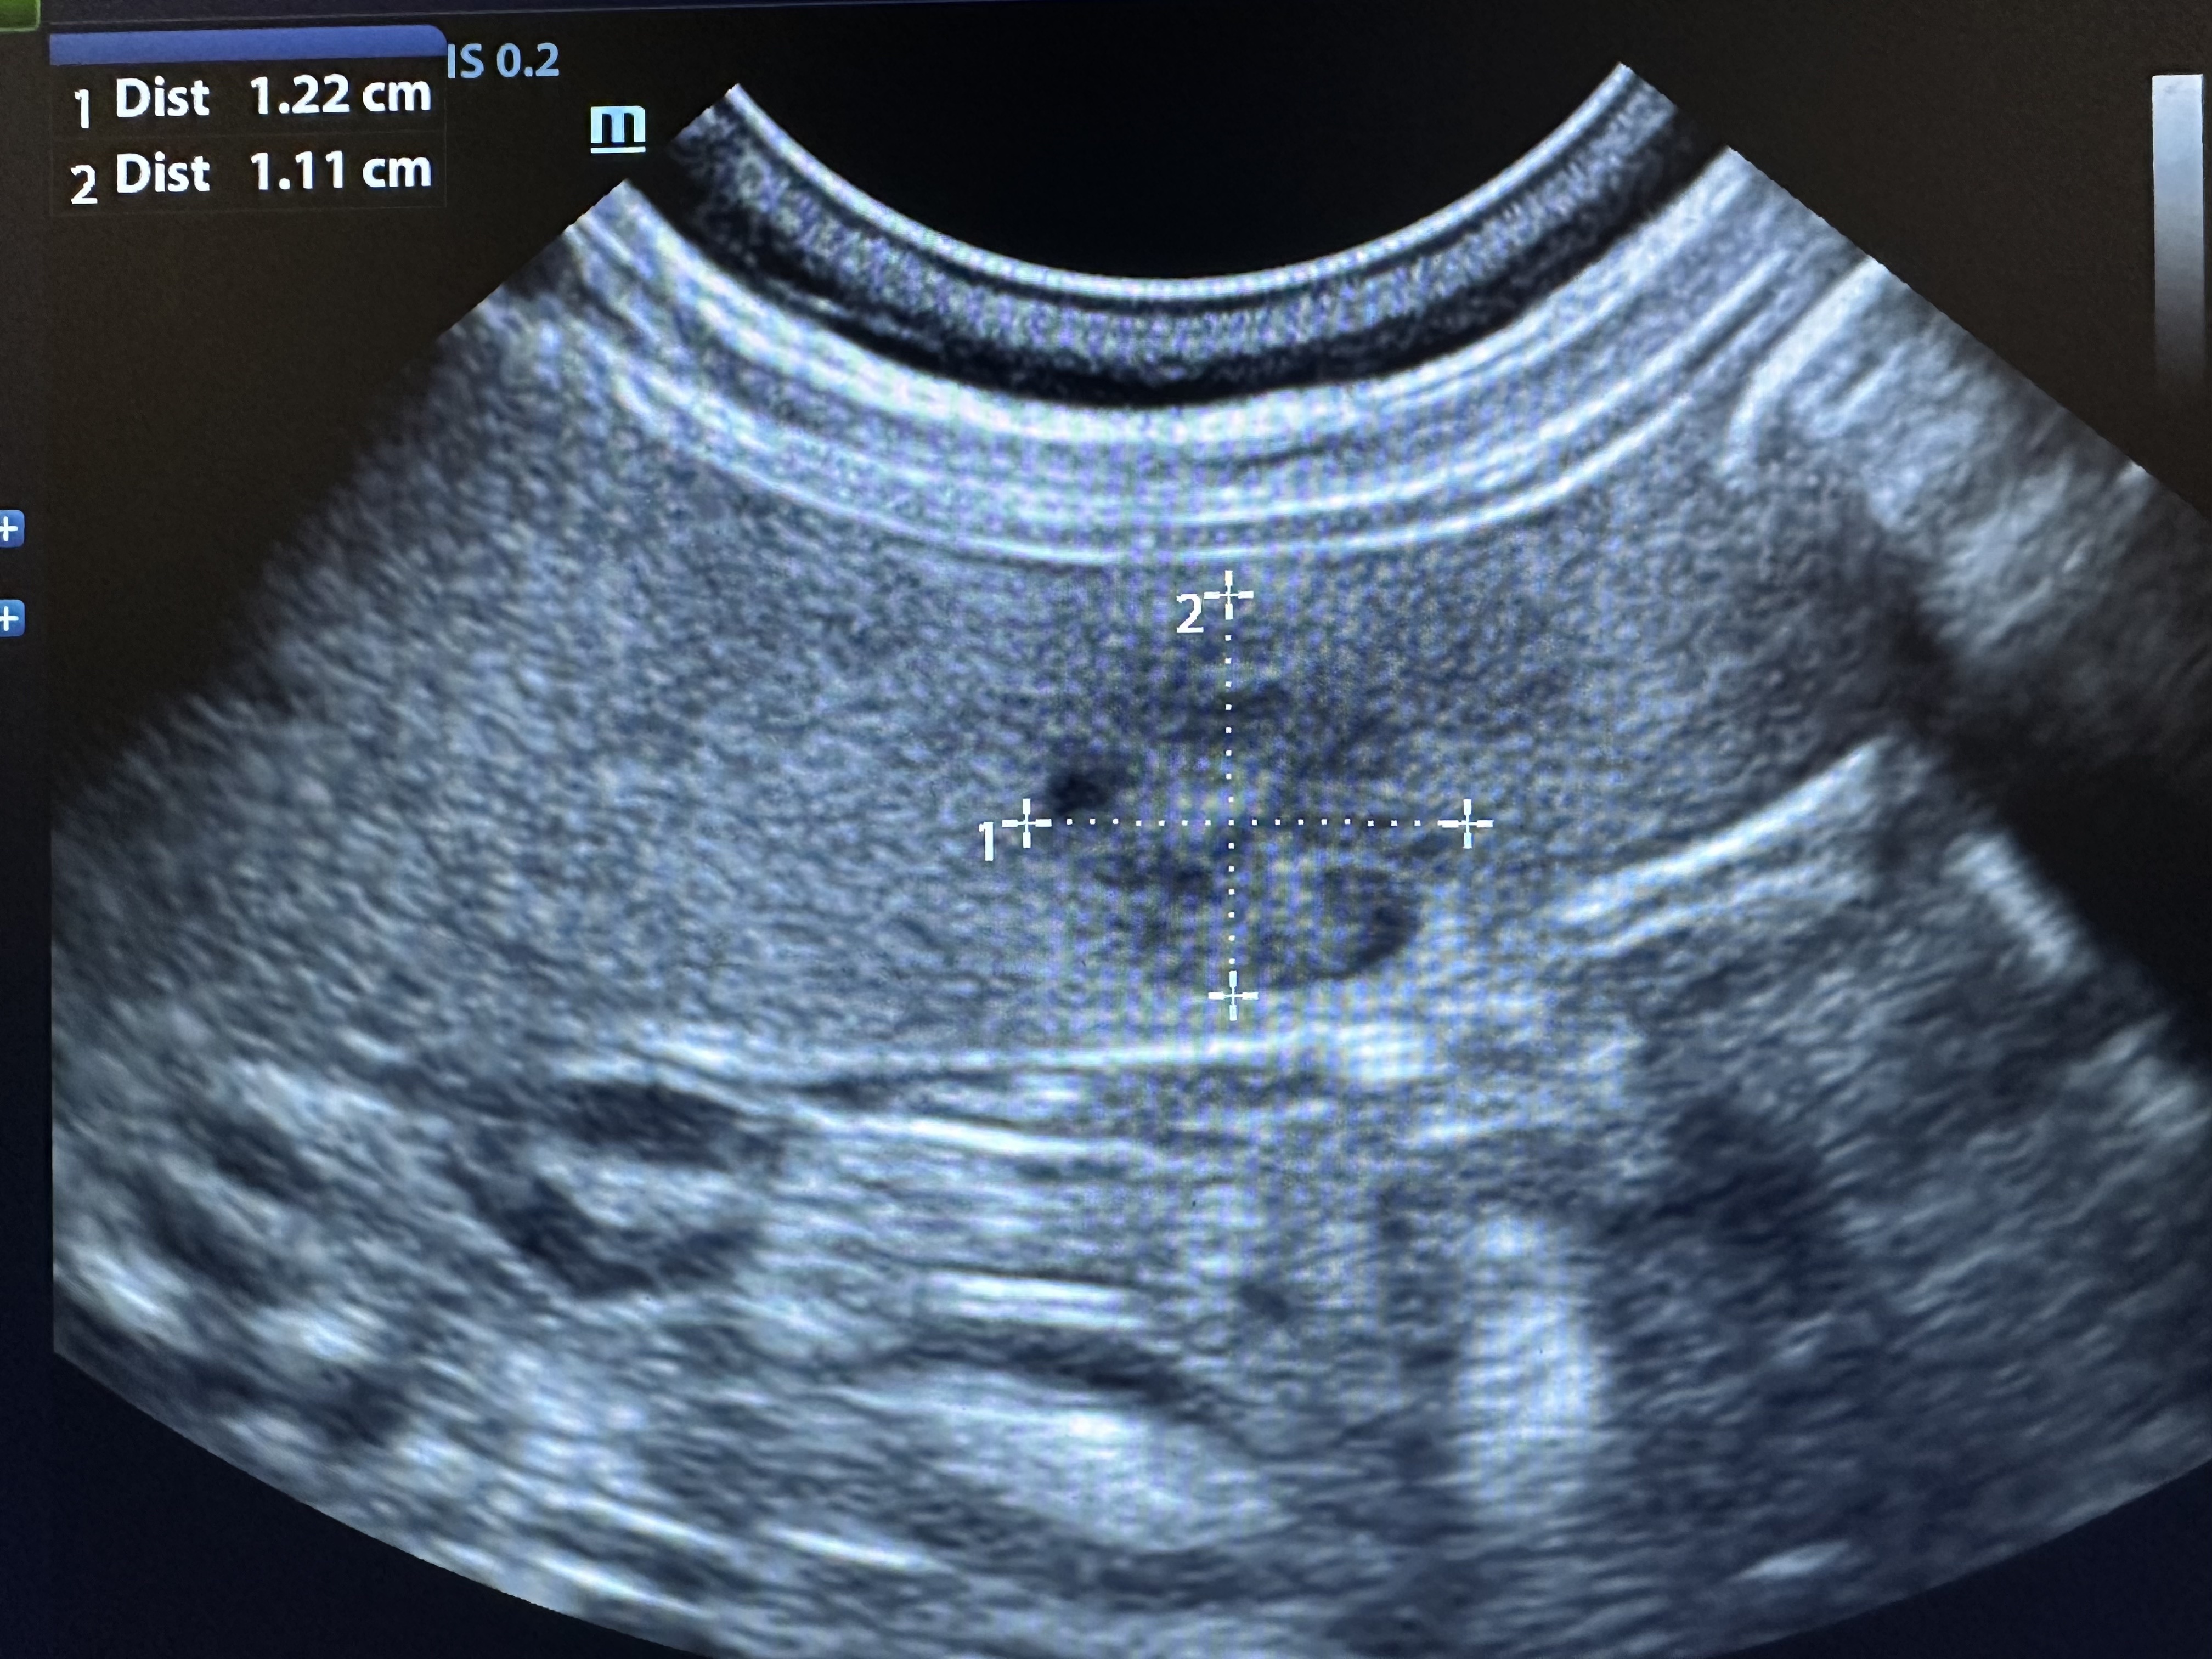

In a healthy dog, the spleen should have a smooth, uniform echotexture on ultrasound. Over time, changes in the spleen can occur—some are benign, like nodules or hyperplasia, while others may signal more serious conditions. The goal of the Spleen Screen is to catch these changes early, before any outward symptoms appear.

Using portable ultrasound equipment, we’ll use sound waves to gently scan your dog’s spleen and provide you with images from the screening. This is a quick and safe process that many dogs tolerate very well, especially in a calm setting.

This is a screening, not a diagnosis. No medical conclusions or treatment recommendations will be made during the event. You will receive the ultrasound images of your dog’s spleen, which you can share with your regular veterinarian for further evaluation or follow-up if needed.